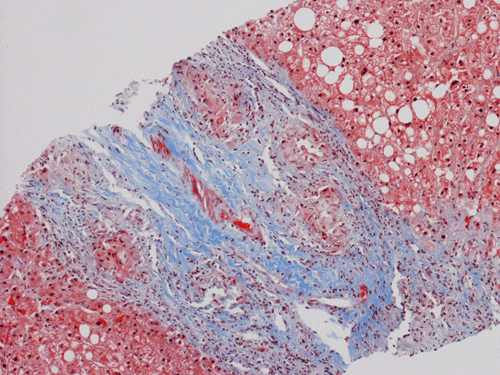

Pathology of the Case: At low magnification, a few small nodules (arrow in Panel A) can be seen with the hematoxylin and eosin stained section. On medium magnification, these nodules correspond to sharply defined granuloma without necrosis. These granuloma are not associated with a high density of lymphocytes in the surrounding liver parenchyma (Panel B and C). Multinucleated giant cells (arrow in Panel C, magnified in Panel D). On reticulin stain, there are reticulin fibers that extends into the granuloma (Panel E). Trichrome stain demonstrated bridging fibrosis (Panel F). The granuloma are well defined and some of them are surrounded by fibrous tissue (Panel G). Immunohistochemistry demonstrated preservation of bile ductules as well as proliferation of ductules (Panle H). No residual ductules are noted in the granuloma as revealed by immunohistochemistry for CK7 (Panel I). Neither acid fast bacilli or fungal organisms are identified by acid fast stain and Gomori's methenamine silver (GMS) stain.

Histopathologic features of sarcoidosis include scattered granulomas in the liver, which may tend to be portal or periportal. Multinucleated giant cells, epithelioid cells, and a variable but usually minimal inflammatory cellular response is present. The granulomas, like in sarcoidosis occuring in other organ systems, tend to be well-demarcated or "clear cut", several granulomas are often comparable in size, and necrosis is not typically present. Asteroid bodies, intracellular vacuolated structures resembling a sea anemone, may be found within the giant cells. Large basophilic, round to roughly oval, and concentrically laminated, Schaumann bodies may be evident in the sarcoid granuloma. None of these inclusions are pathognomonic feature of sarcoidosis, however, do suggest this diagnosis. Ductopenia, cholestasis and features of chronic cholestasis resembling PBC have been described in the cases of sarcoidosis. Severe fibrosis and cirrhosis in conjunction with portal hypertension may be present in sarcoidosis. End stage liver disease in sarcoidosis has been successfully treated by orthotopic liver transplant and recurrent disease has been reported in one such case. Reticulin fibers has a tendency to extend into the granulomas as illustrated in this case.